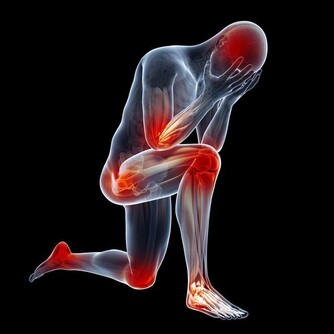

頸椎病除了有脖子僵硬、肩膀酸痛等症狀,還會連累全身多個部位,並用一些“狡猾”的症狀蒙蔽你。

而且,頸椎病如果不及時治療,患者可能出現四肢麻木、疼痛、跛行等症狀。